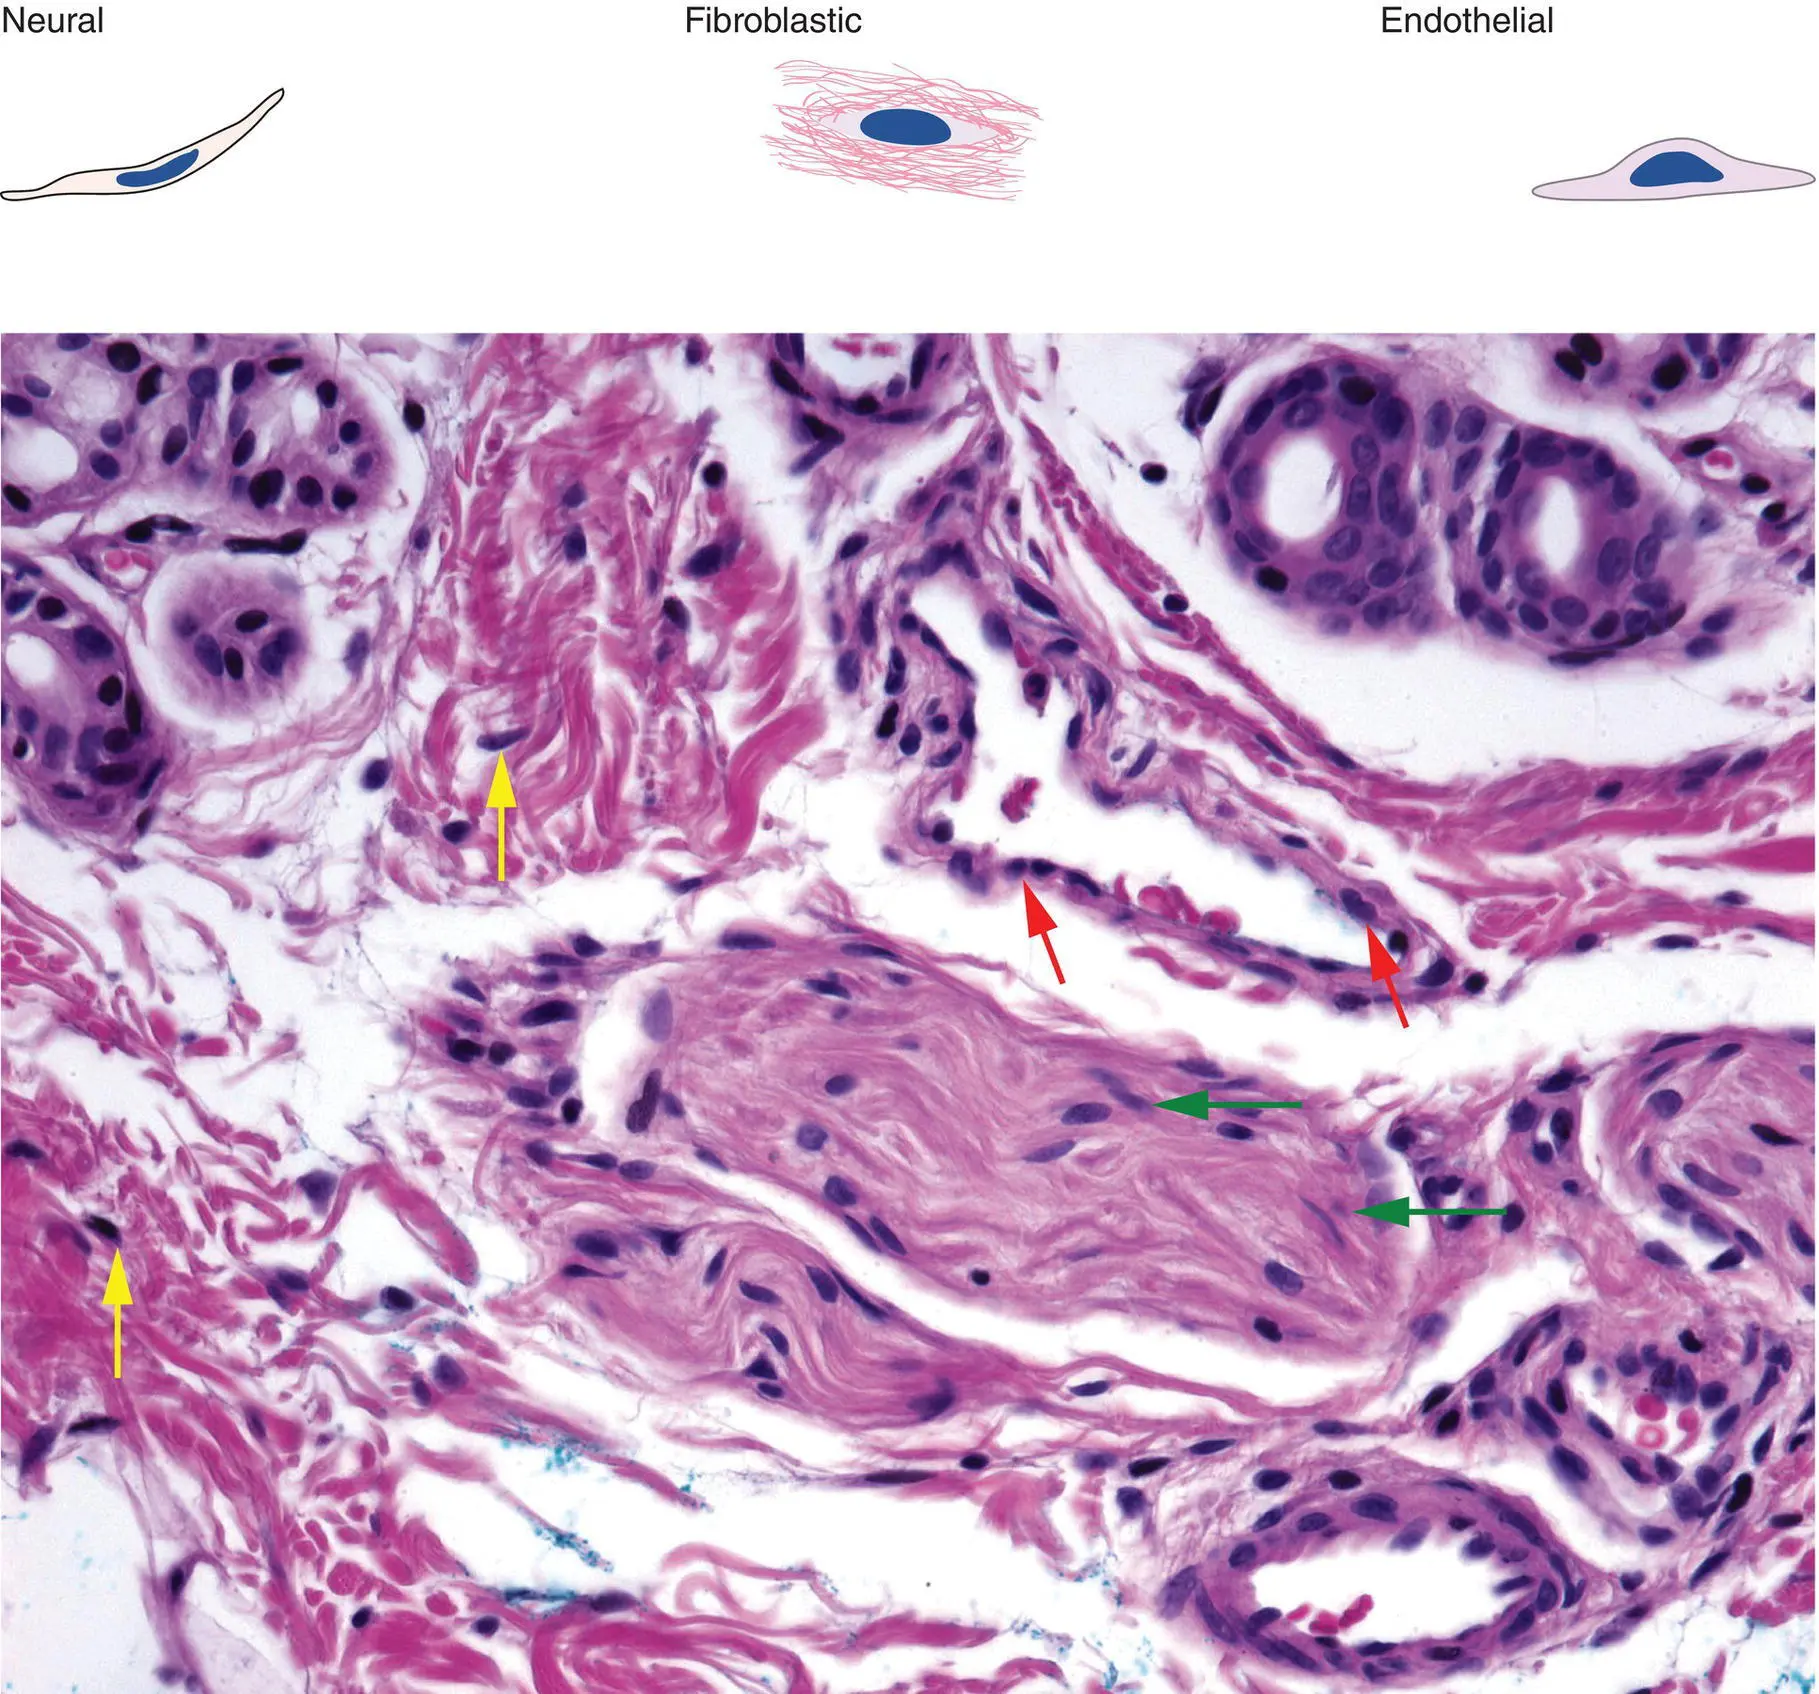

Figure 2(C)Different tumors are predominantly composed of a particular cell type

Neural: spindle cell with tapered nucleus, pink cytoplasm (green arrows)

Fibroblast: spindle cell with oval nucleus (yellow arrows)

Endothelial: blue nuclei surrounding vascular spaces (red arrows)